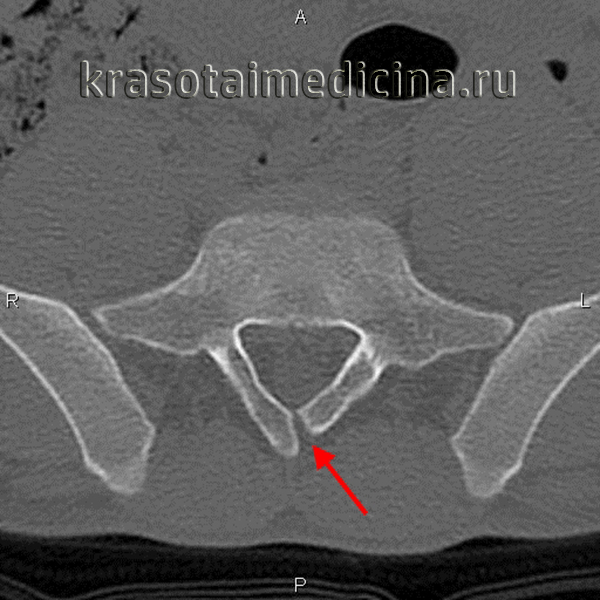

(Слева) На рентгенограмме пояснично-крестцового отдела в прямой проекции (исследование выполнено по поводу болевого синдрома в нижней части спины) случайной находкой стало неполное заращение пластинки дуги S1.

(Справа) На аксиальном Т1-ВИ видно типичное неполное слияние задних элементов позвонка по срединной линии. Эта находка стала случайной в ходе проведения обследования пациента по поводу болевого синдрома в нижней части спины. (Слева) КТ, фронтальный срез: признаки косого асимметричного расположения пластинок дуги L5 позвонка, наслаивающихся друг на друга, — та -кая конфигурация приводит к ротационной перегрузке дугоотростчатых суставов и преждевременной их дегенерации.

(Справа) КТ, аксиальный срез на уровне пояснично-крестцового перехода: у пациента с косым расположением ротацией и неполным слиянием задних элементов позвонка дополнительно выявлен дефект межсуставной части дуги L5 (без дислокации), возникший, возможно, на фоне ротационной перегрузки межсуставной части дуги.

о Неполное слияние задних элементов позвонка по срединной линии, края дефекта закруглены, имеют четко выраженный кортикальный слой, могут наслаиваться друг на друга

3. КТ признаки неполного слияния позвонка (spina bifida occulta):

о Незаращение остистого отроака/плааинки дуги